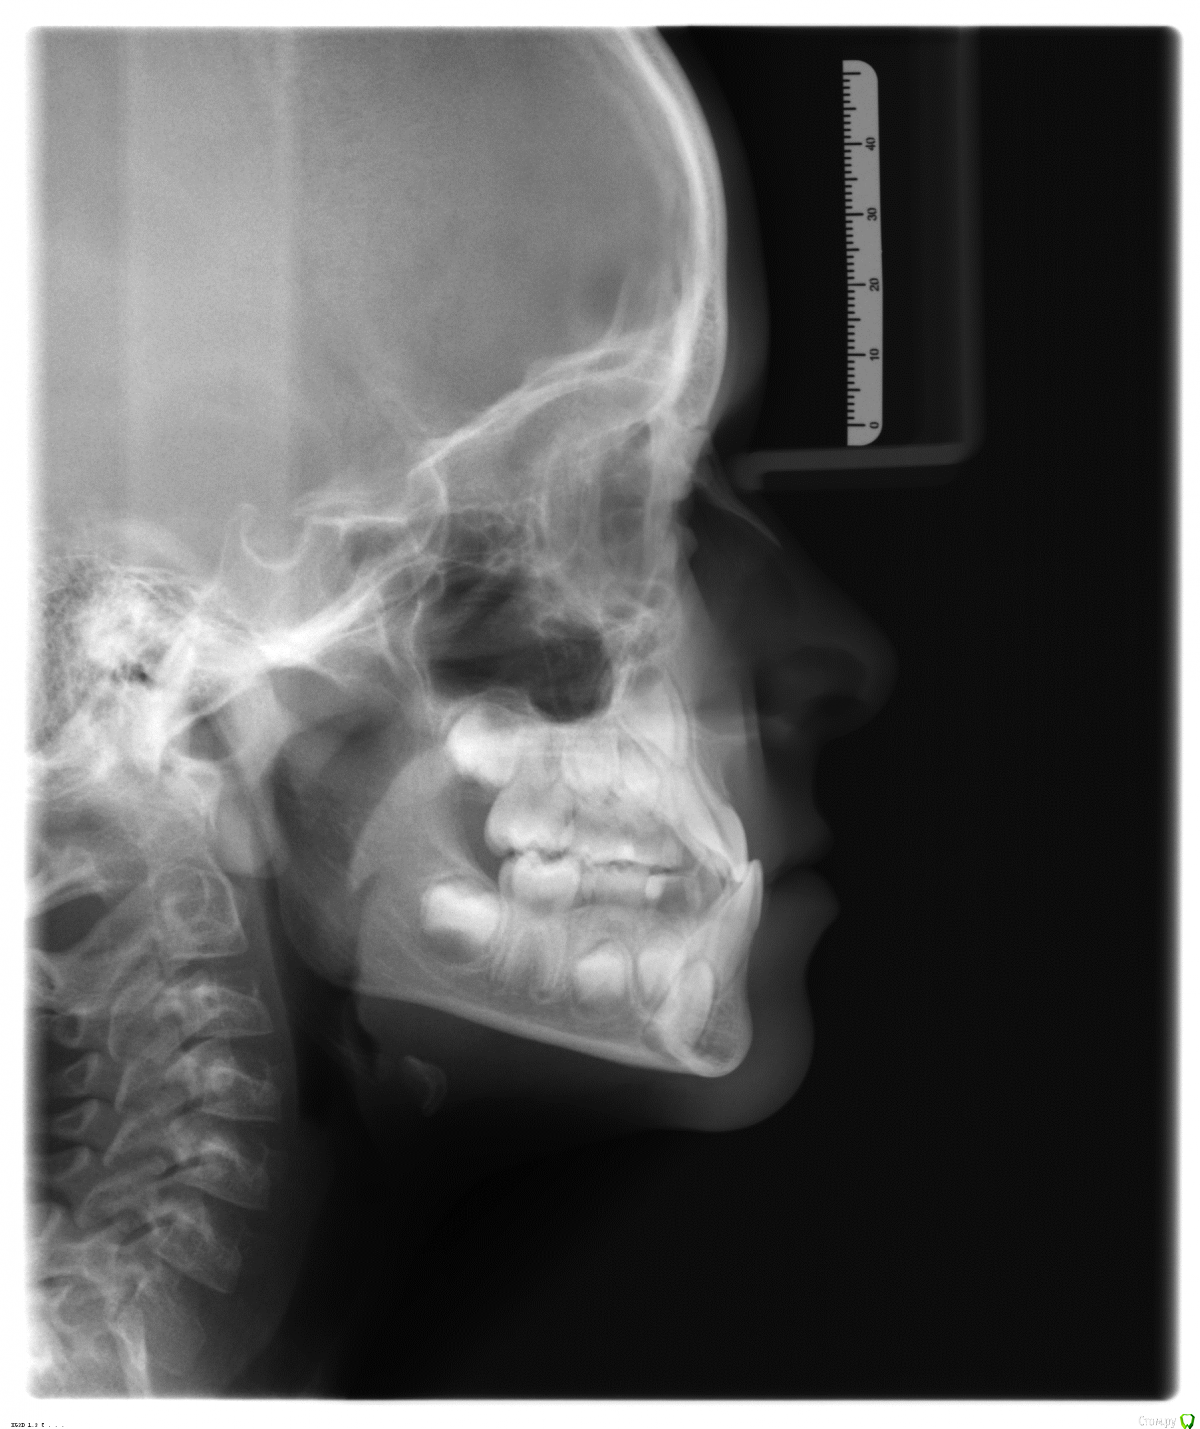

Светка255 Опубликовано 2 февраля, 2016 Поделиться Опубликовано 2 февраля, 2016 Здравствуйте, уважаемые врачи!Ребёнок, 8 лет, мезиальный прикус. Есть два различных мнения по поводу исправления:1). ночная капа OCCLUS-O-GUIDE.2). аппарат Брюкля.Мне сложно определиться, я не специалист, поэтому прошу ваших мнений и комментариев.Заранее спасибо! Ссылка на комментарий